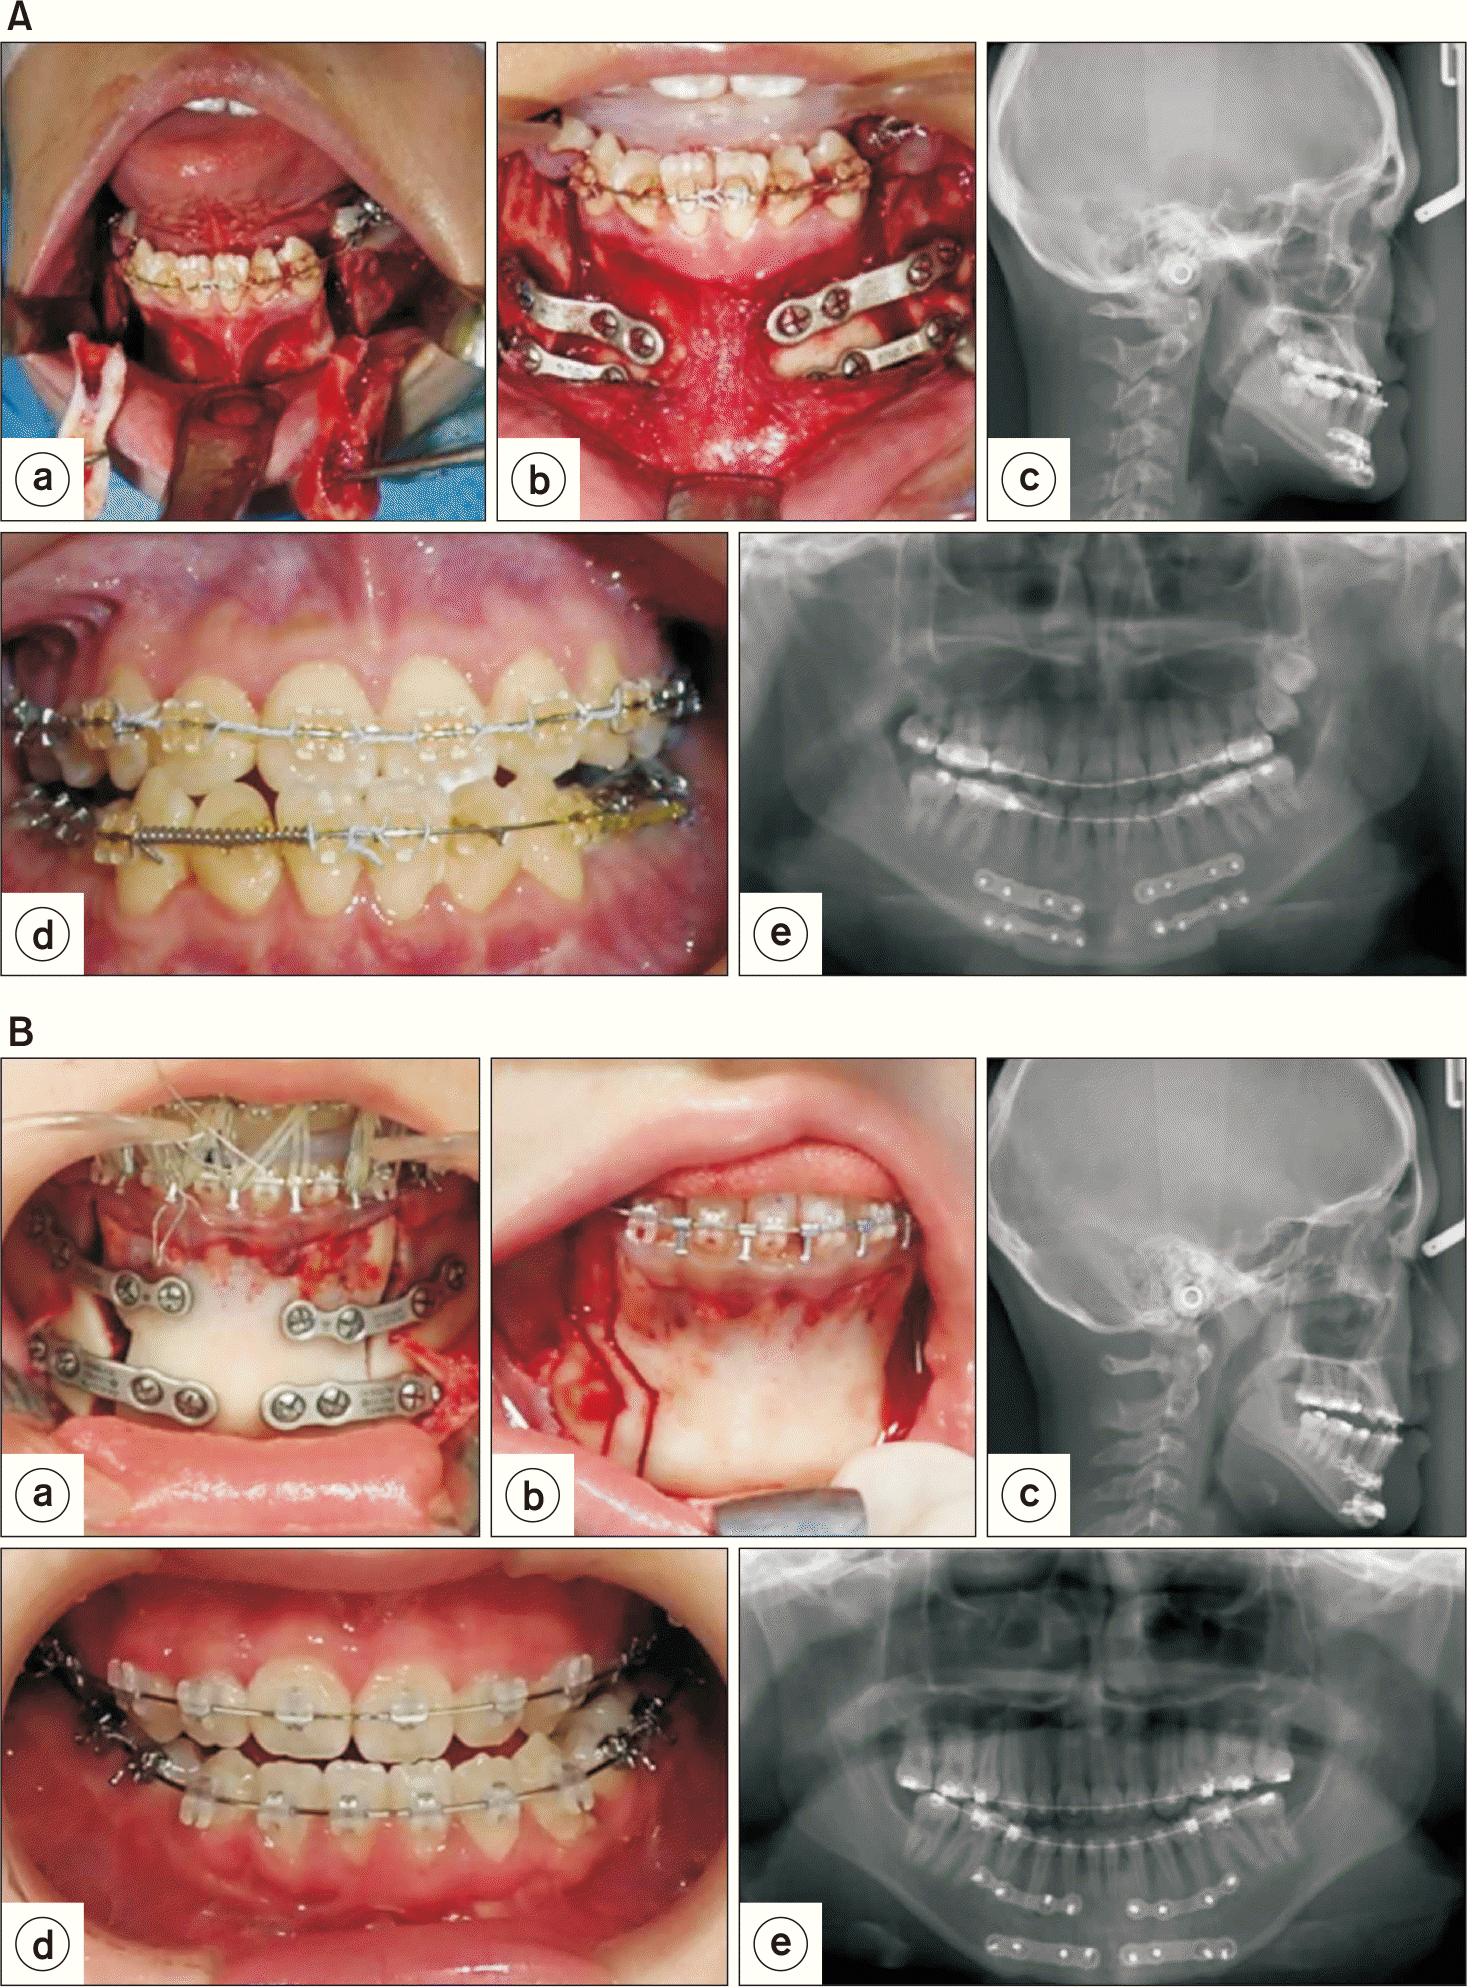

Fig. 2

A. First stage surgery for Patient 1: Modified Dingman’s anterior mandibular body osteotomy with step. (a) Bilateral Dingman’s anterior mandibular body osteotomy with step, (b) fixation with titanium osteosynthesis, (c) lateral cephalograph, (d) occlusion, and (e) orthopantomograph. B. First stage surgery for Patient 2: Modified Dingman’s mandibular body osteotomy with step. (a) Bilateral Dingman’s anterior mandibular body osteotomy with step, (b) fixation with titanium osteosynthesis, (c) lateral cephalograph, (d) occlusion, and (e) orthopantomograph.